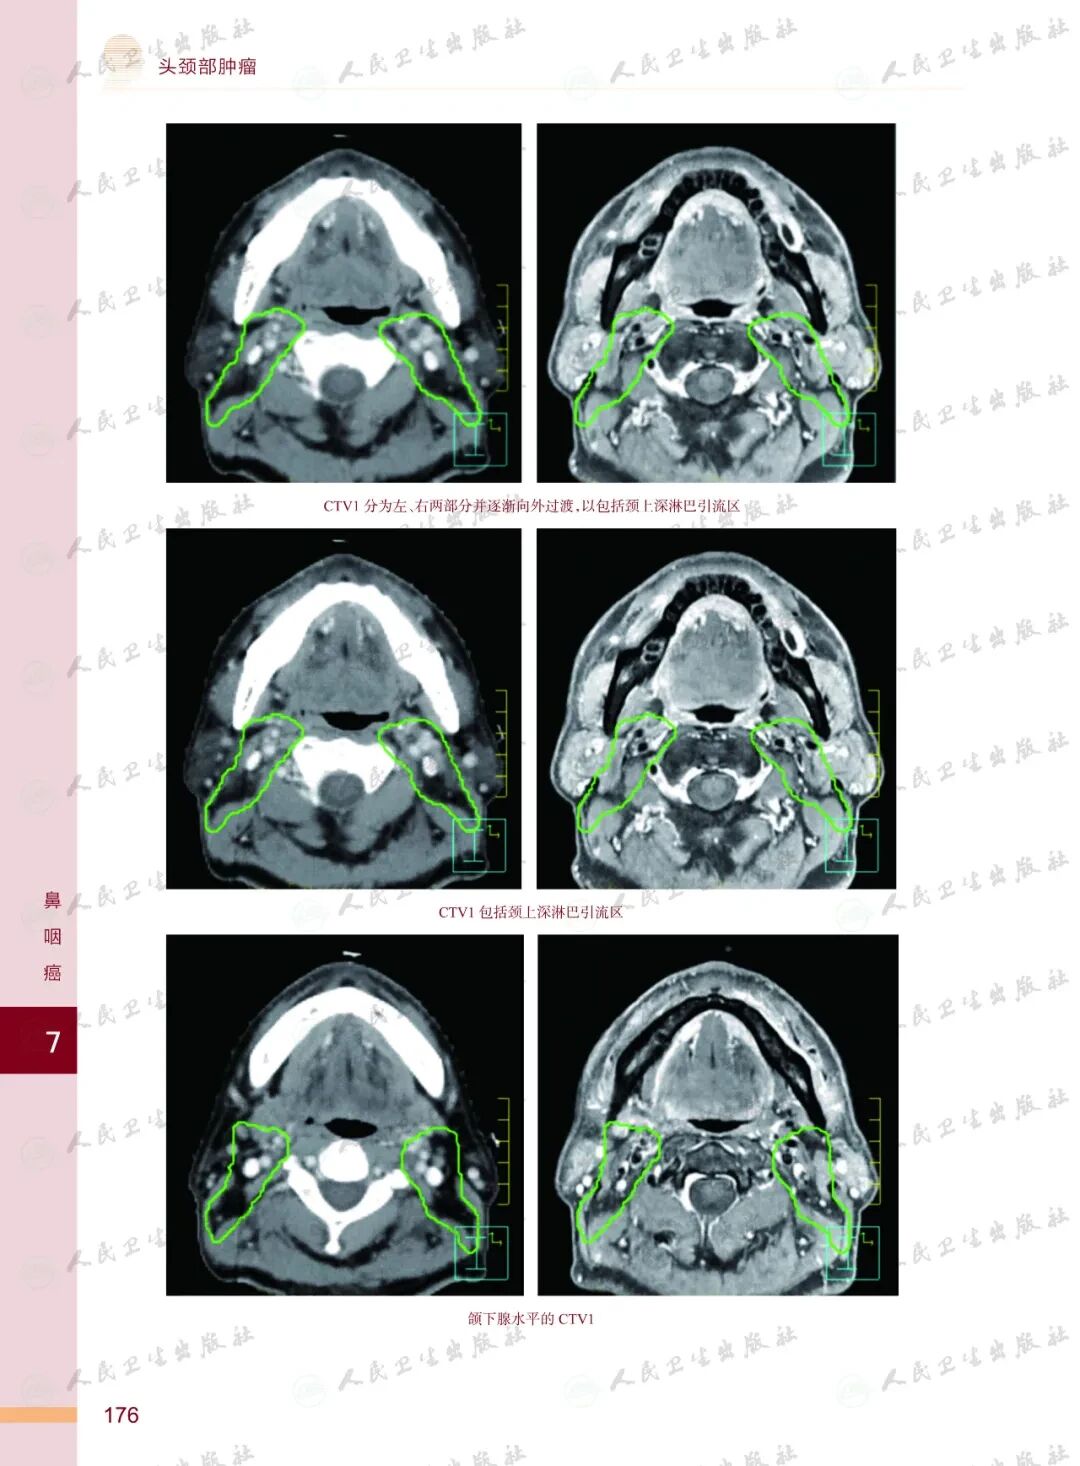

《头颈部肿瘤放射治疗图谱》

——不止是图谱,更是随唤随应的临床良师

样章试读